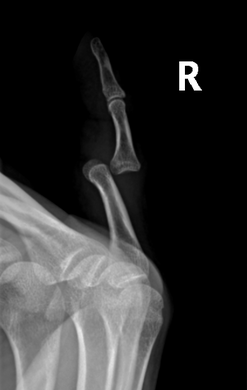

Radiograph of right fifth phalanx bone dislocation- Radiograph of left index finger dislocation